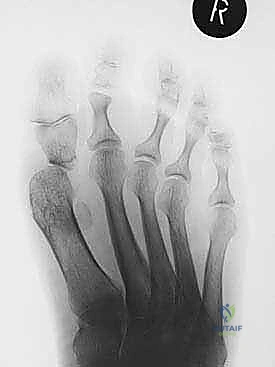

- التصوير بالأشعة السينية (X-rays): صور في وضعية الوقوف (تحمل الوزن) من زوايا متعددة لقياس زوايا التشوه بدقة وحساب مقدار الطول المفقود.

- التصوير المقطعي المحوسب (CT Scan): ضروري جداً لتكوين صورة ثلاثية الأبعاد للعظم المتبقي، ولتخطيط حجم وشكل الطعم العظمي المطلوب.